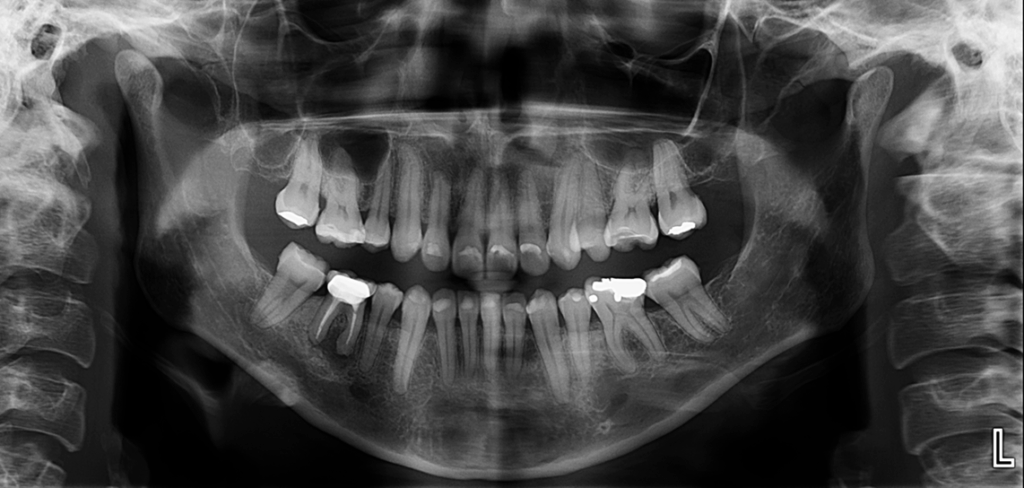

Radiografia Panorámica

En la radiografía panorámica se evidencian múltiples restauraciones coronarias, así como presencia de placa cervical mineralizada de forma generalizada.

En relación con la pieza 46, se observa tratamiento endodóntico, hipercementosis y un proceso osteolítico periapical, que presenta un aumento de la densidad ósea circundante.